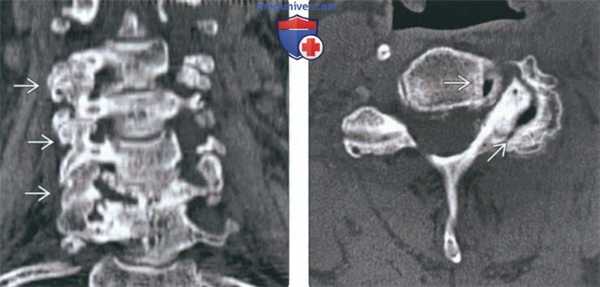

(Слева) КТ, фронтальный срез: признаки выраженной многоуровневой дегенеративной гипертрофической артропатии дугоотростчатых суставов с фораминальным стенозом.

(Справа) КТ, аксиальный срез: признаки выраженного дегенеративного поражения левого дугоотростчатого сустава и фораминального стеноза. В полости дугоотростчатого и унковертебрального сустава отмечается «феномен вакуума».

(Слева) На корональной КТ без КУ определяется тяжелая многоуровневая гипертрофическая дегенеративная артропатия дугоотростчатых суставов со стенозом межпозвонковых отверстий.

(Справа) На аксиальной КТ без КУ определяется тяжелая левосторонняя дегенеративная артропатия дугоотростчатого сустава со стенозом межпозвонкового отверстия. Определяется вакуум - феномен дугоотростчатого сустава и унковертебрального сустава.